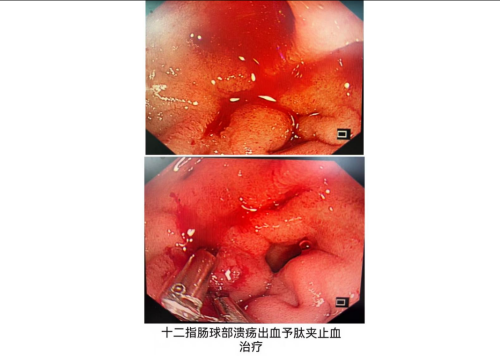

近期,38岁的李勇(化名)因黑便3天、呕血3小时,在家中摔倒后被紧急送往香港马会app (南华大学附属香港马会app )。经消化内科行急诊胃镜检查,诊断十二指肠球部多发溃疡并出血,经内镜下止血治疗及内科药物治疗后稳住病情。后续检查又揪出十二指肠球部溃疡的“元凶”——幽门螺旋杆菌感染,医生判断,李先生平日聚餐较多,且从不使用公筷,这极可能是感染幽门螺旋杆菌的重要原因。

“患者平时聚餐频繁,饮食不规律,也没重视过胃部的不适,更没做过相关检查,根本不知道自己感染了幽门螺旋杆菌,还患上了消化性溃疡。这次发病前又参加朋友聚餐,饮酒加辛辣食物等综合因素,最终导致消化性溃疡出血”。据该院消化内科副主任、主任医师易艳容介绍,李先生的情况并非个例,很多人都像他一样,经常聚餐,且聚餐时无使用公筷的意识,可能存在幽门螺旋杆菌的交叉传播感染。